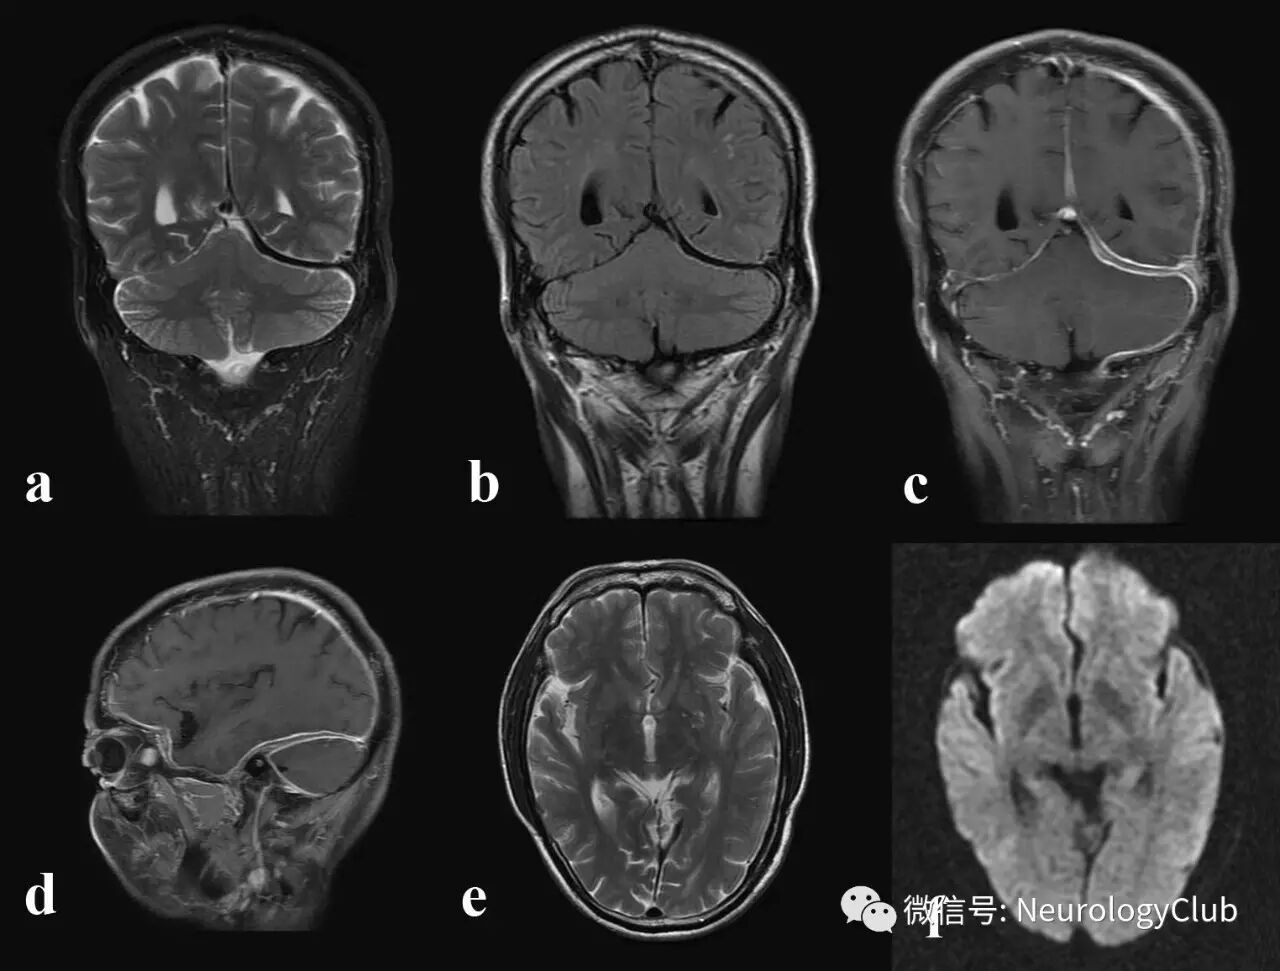

图1:特发性肥厚性硬脑膜炎患者;可见肥厚的硬脑膜在T2WI(a,e)上呈低信号,FLAIR(b)和DWI(f)上亦为低信号;T1增强(c,d)可见硬脑膜(左侧>右侧)明显不对称性强化;左侧小脑幕处硬脑膜中心线样无强化,两侧周边轨道样强化,即“轨道征”